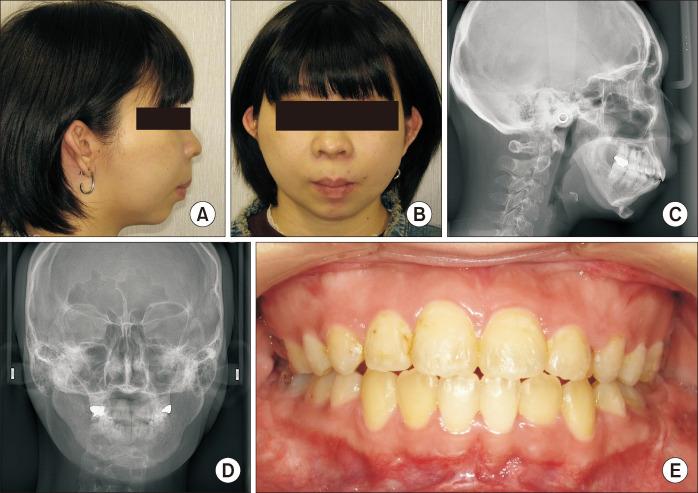

Untreated mandibular condyle fractures in childhood can result in significant jaw deformities, such as mandibular retrognathism, open bite, and facial asymmetry, which may necessitate surgical intervention in later years. Surgical approaches vary depending on the severity of the condition, including mandibular surgery alone, maxillomandibular surgery, or mandibular distraction osteogenesis (MDO). This report highlights a case involving mandibular retrognathism and open bite with condylar dislocation and malunion caused by untreated pediatric condyle fractures. Key challenges in this case included excessive anterior mandibular movement, irregular morphology of the mandibular ramus caused by malunion from fracture healing, and anteromedial dislocation of both condyles, all of which posed significant surgical complexities. The surgical approach combined Le Fort I osteotomy with MDO to perform maxillary impaction and mandibular advancement, followed by a secondary genioplasty. Notably, the dislocated temporomandibular joints were left untreated. Two years postoperatively, no relapse or recurrence of open bite was observed, and the dislocated condyles showed no positional and morphological changes, reflecting favorable outcomes. To our knowledge, this is the first reported case of orthognathic surgery combined with MDO for bilateral dislocated mandibular condyles, making it a valuable contribution to clinical practice.

儿童期未经治疗的下颌髁突骨折可导致严重的颌骨畸形,如下颌后缩、开颌和面部不对称,这可能在日后需要手术干预。手术方法因病情严重程度而异,包括单纯下颌手术、上颌下颌联合手术或下颌骨牵张成骨术(MDO)。本报告重点介绍了一例因儿童期髁突骨折未经治疗导致下颌后缩、开颌伴髁突脱位和骨不连的病例。该病例的主要挑战包括下颌前部过度移动、骨折愈合导致的骨不连引起的下颌升支形态不规则以及双侧髁突向前内侧脱位,所有这些都带来了重大的手术复杂性。手术方法结合了Le Fort I截骨术和MDO,以进行上颌骨上移和下颌骨前徙,随后进行二期颏成形术。值得注意的是,脱位的颞下颌关节未进行治疗。术后两年,未观察到开颌复发或再发,脱位的髁突也未出现位置和形态变化,显示出良好的效果。据我们所知,这是首例报道的正颌手术联合MDO治疗双侧脱位下颌髁突的病例,对临床实践具有重要价值。